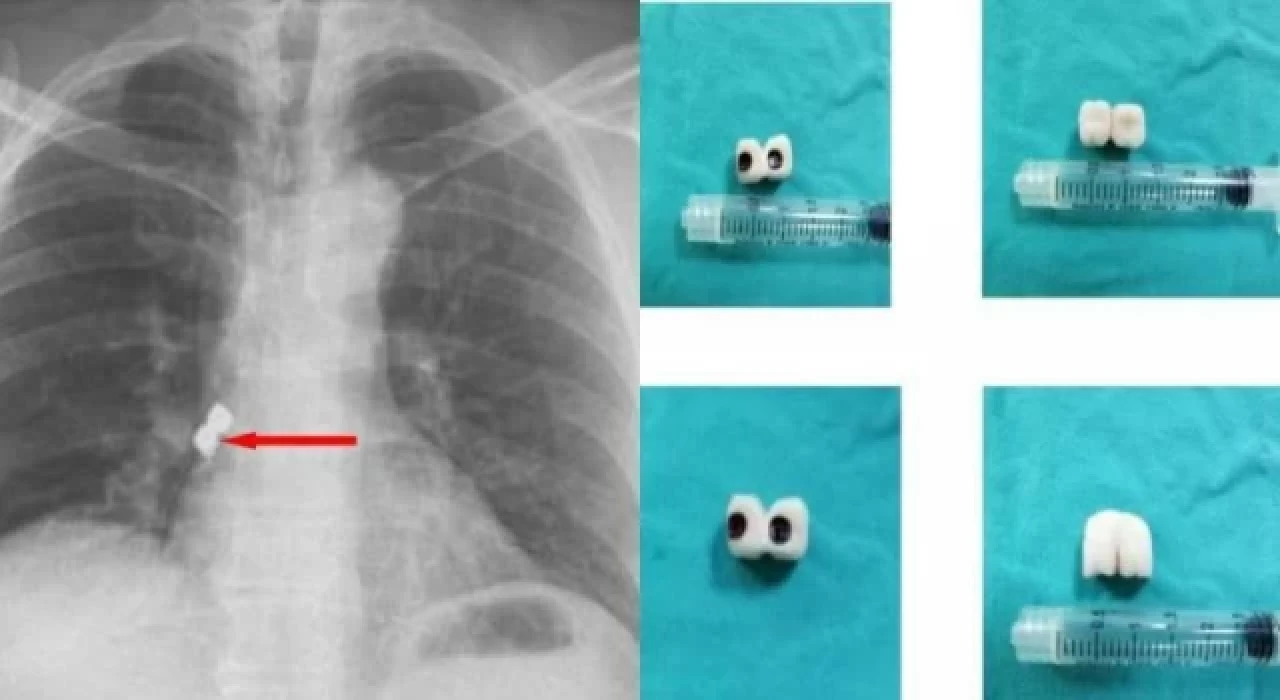

Afyonkarahisar’da, diş tedavisi gören bir şahsın soluk borusuna 2 implant kaçtı. İmplantlar, hastanın akciğer girişinden çıkarıldı.

Afyonkarahisar’da, bir şahsın diş tedavisi sırasında soluk borusuna kaçan iki implant başarıyla alındı.

Belçika’da yaşayan 56 yaşındaki Demet Kaplan, geldiği Emirdağ ilçesinde diş tedavisi için bir kliniğe gitti.

Operasyon sırasında birbirine yapışık olan 2 implant hastanın dişinden düştü.

Kaplan, yutkununca implantlar soluk borusuna kaçarak burayı tıkadı.

Nefes almakta zorlanan Kaplan, Emirdağ Devlet Hastanesi’nde yapılan ilk müdahalenin ardından Afyonkarahisar’da başka bir hastaneye sevk edildi.

İmplantlar, Kaplan’ın akciğer girişinden çıkarıldı.